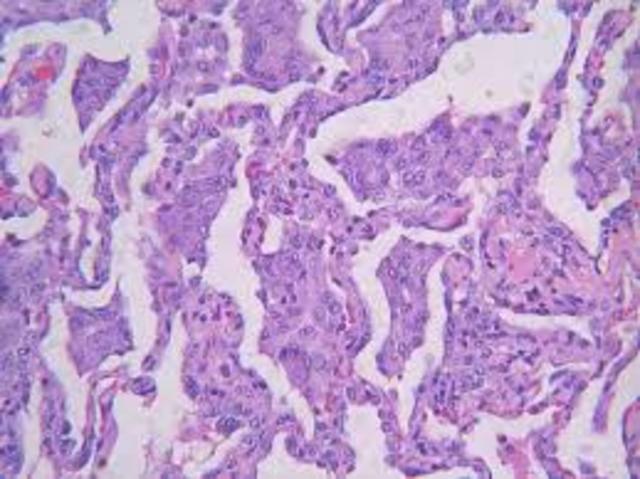

Mycobacterium fortuitum es una micobacteria no tuberculosa (MNT), una agrupación que engloba todas las micobacterias fuera del complejo Mycobacterium tuberculosis. M fortuitum se clasifica en el grupo IV Runyon, micobacterias de crecimiento rápido. [1] Se ha encontrado en las fuentes de agua naturales y procesados, así como en las aguas residuales y la suciedad. La distribución es probablemente todo el mundo.